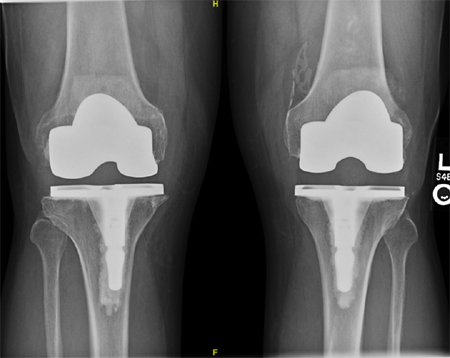

人工全膝关节置换术后x线片

膝关节假体是由金属与聚乙烯材料制成,这些在运动中相接触的材料会不可避免的产生划痕、氧化、剥脱,进而逐渐磨损。尽管膝关节假体理论上的设计寿命很长,但它们不可能永久使用下去。膝关节置换的实际目标是实现可以良好使用几十年的膝关节,这样足以满足大多数患者的需要。大多数研究表明,常见的膝关节假体系统能使用超过20年。一项研究表明,膝关节置入20年后,96%的假体仍然功能完好。但是即便现代膝关节置换技术已经取得长足进步,患者需要了解的是,因为感染、骨折、不稳定、松动等原因,膝关节置换必然会有一定的失败率。失败的膝关节置换就会需要进行翻修手术,而翻修术后的效果通常不如初次置换那么令人满意。对于患者来说,在正规医院进行初次置换术,获得良好的初次效果,对于延长人工膝关节的寿命,是非常重要的。